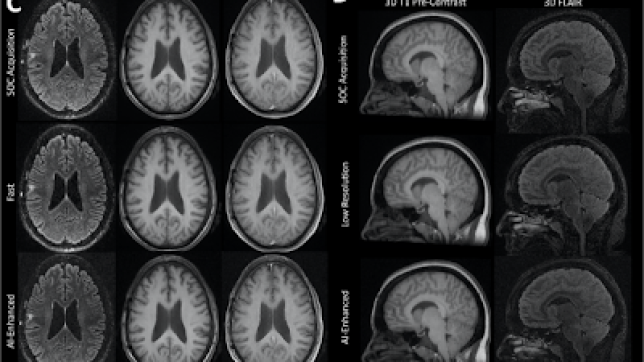

Using AI-Based Image Enhancement to Reduce Brain MRI Scan Times and Improve SNR